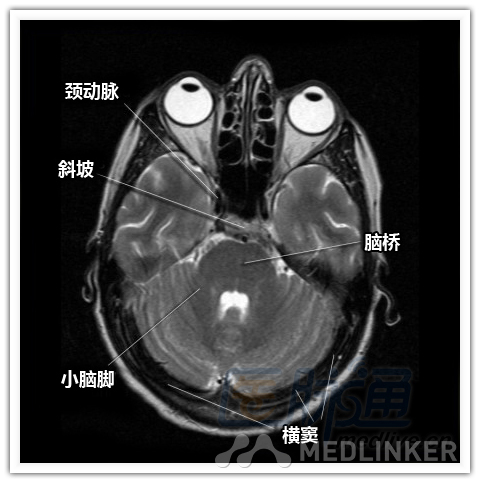

简明易懂的脑部断层解剖:横断位MRI(1)

本文将对不同横断位的脑部MRI图像进行标示,主要讲解内容是脑部基本解剖。脑部横断位解剖,尤其是内囊层面的影像学解剖一直是一大重点,一起来学习一下。 横断位图像顺序:由足侧至头侧 本文转载自医脉通。 声明:本文转载是出于提供更多信息以参考使用或学习、交流之目的,不用于商业用途。转载无意侵犯版权,如转载文章涉及您的权益等问题,请作者速来告知,我们将尽快做删除处理。